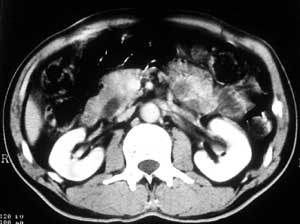

患者,男,57岁,梗阻性黄疸10余天。

这个病例胰头无明显增大,胆总管扩张明显而肝内胆管扩张更不明显,病程较短,

注意到十二指肠乳头明显突出,但尚光滑。分析以下可能性:

1、十二指肠乳头本身的病变,如乳头炎症;

2、急性乳头水肿,胆总管下端结石排石后乳头水肿;

3、壶腹部胆总管下端肿瘤累及十二指肠乳头。

十二指肠乳头粘膜慢性非特异性炎症